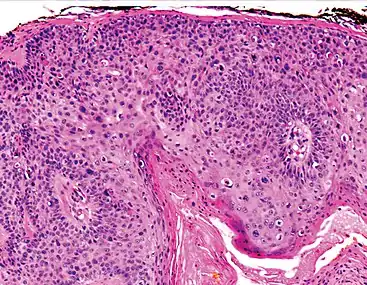

Histopathologically, the epidermis in cSCC in situ (Bowen's disease) will show hyperkeratosis and parakeratosis. There will also be marked acanthosis with elongation and thickening of the rete ridges. These changes will overly keratinocytic cells which are often highly atypical and may in fact have a more unusual appearance than invasive cSCC. The atypia spans the full thickness of the epidermis, with the keratinocytes demonstrating intense mitotic activity, pleomorphism, and greatly enlarged nuclei. They will also show a loss of maturity and polarity, giving the epidermis a disordered or "windblown" appearance.

Two types of multinucleated cells may be seen: the first will present as a multinucleated giant cell, and the second will appear as a dyskeratotic cell engulfed in the cytoplasm of a keratinocyte. Occasionally, cells of the upper epidermis will undergo vacuolization, demonstrating an abundant and strongly eosinophilic cytoplasm. There may be a mild to moderate lymphohistiocytic infiltrate detected in the upper dermis.[12]

Histopathology of squamous-cell carcinoma in situ (black arrow), compared to normal skin, showing marked atypia.

Squamous-cell carcinoma in situ, showing prominent dyskeratosis and aberrant mitoses at all levels of the epidermis, along with marked parakeratosis.[12]